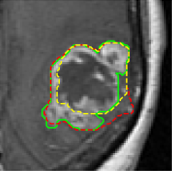

We first introduce a method for connecting the output of a CNN to an ACM, yielding a model for the precise delineation of lesions, to which we refer as Deep Active Lesion Segmentation (DALS) (Figure 4). We then go further to introduce a truly unified framework (Figure 5) that bridges the gap between ACMs and CNNs by leveraging a novel, automatically differentiable level-set ACM with trainable parameters that allows for back-propagation of gradients and can be end-to-end trained along with a backbone CNN from scratch, without any CNN pre-training. The ACM is initialized directly by the CNN and utilizes an energy functional that is locally-tunable by the backbone CNN, through 2D feature maps. Thus, our work overcomes the big hurdle of fully automating the powerful ACM approach to image segmentation. We have applied our proposed framework to the task of building segmentation in aerial images (Figure 6).

Deep Active Lesion Segmentation

[45]: Lesion segmentation is an important problem in computer-assisted diagnosis that remains challenging due to the prevalence of low contrast, irregular boundaries that are unamenable to shape priors. We introduce Deep Active Lesion Segmentation (DALS), a fully automated segmentation framework that leverages the powerful nonlinear feature extraction abilities of FCNs and the precise boundary delineation abilities of ACMs. Our DALS framework benefits from an improved level-set ACM formulation with a per-pixel-parameterized energy functional and a novel multiscale encoder-decoder CNN that learns an initialization probability map along with parameter maps for the ACM. We evaluate our lesion segmentation model on a new Multiorgan Lesion Segmentation (MLS) dataset that contains images of various organs, including brain, liver, and lung, across different imaging modalities—MR and CT. Our results demonstrate favorable performance compared to competing methods, especially for small training datasets. -

First, we introduce a fully automatic framework for medical image segmentation that combines the strengths of CNNs and level-set ACMs to overcome their respective weaknesses. We apply our proposed Deep Active Lesion Segmentation (DALS) framework to the challenging problem of segmenting lesions in MR and CT medical images, dealing with lesions of substantially different sizes within a single framework. In particular, our proposed encoder-decoder architecture learns to localize the lesion and generates an initial attention map along with associated parameter maps, thus instantiating a level-set ACM in which every location on the contour has local parameter values.

By automatically initializing and tuning the segmentation process of the level-set ACM, our DALS yields significantly more accurate boundaries in comparison to conventional CNNs and can reliably segment lesions of various sizes.

Our DALS framework is illustrated in Figure 3. The boundaries of the segmentation map generated by the encoder-decoder are fine-tuned by the level-set ACM that takes advantage of information in the CNN maps to set the per-pixel parameters and initialize the contour. The input image is fed into the encoder-decoder, which localizes the lesion and, after convolutional and sigmoid layers, produces the initial segmentation probability map , which specifies the probability that any point lies in the interior of the lesion. The Transformer converts to a Signed Distance Map (SDM) that initializes the level-set ACM. Map is also utilized to estimate the parameter functions and in the energy functional (7). Extending the approach of Hoogi et al. [54], the functions in Figure 3 are chosen as follows:

| (16) |

The exponential amplifies the range of values that the functions can take. These computations are performed for each point on the zero level set contour . During training, and the ground truth map are fed into a Dice loss function and the error is back-propagated accordingly. During inference, a forward pass through the encoder-decoder and level-set ACM results in a final SDM, which is converted back into a probability map by a sigmoid layer, thus producing the final segmentation map .